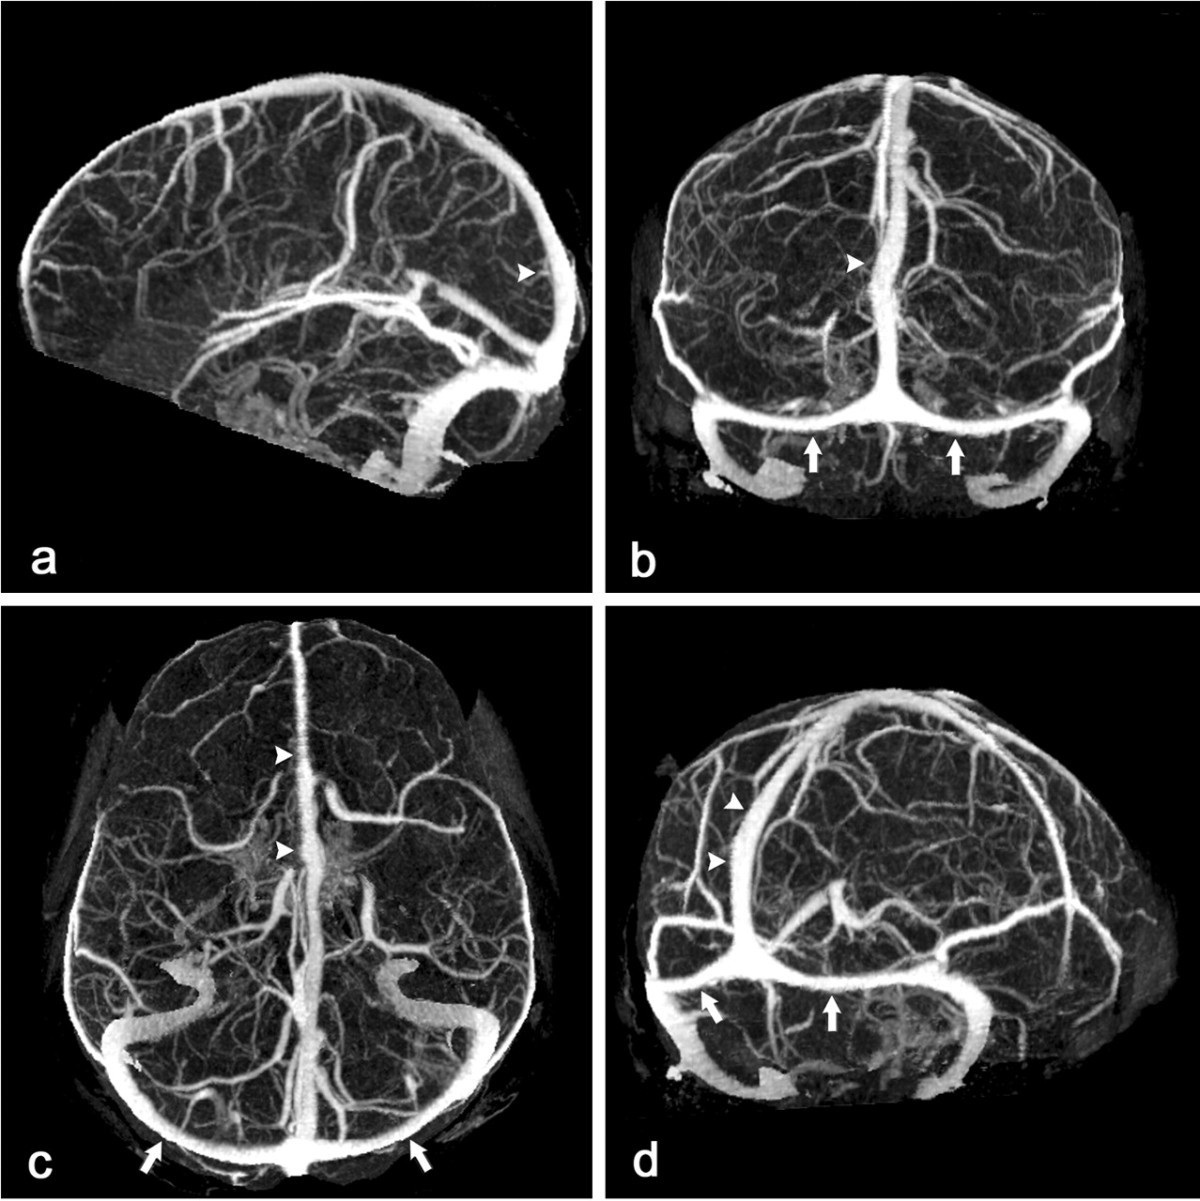

MR Venography

Investigation of choice in suspected Cerebral Venous sinus

thrombosis. Can show obstructed sinus and thrombosis within and absence

of flow